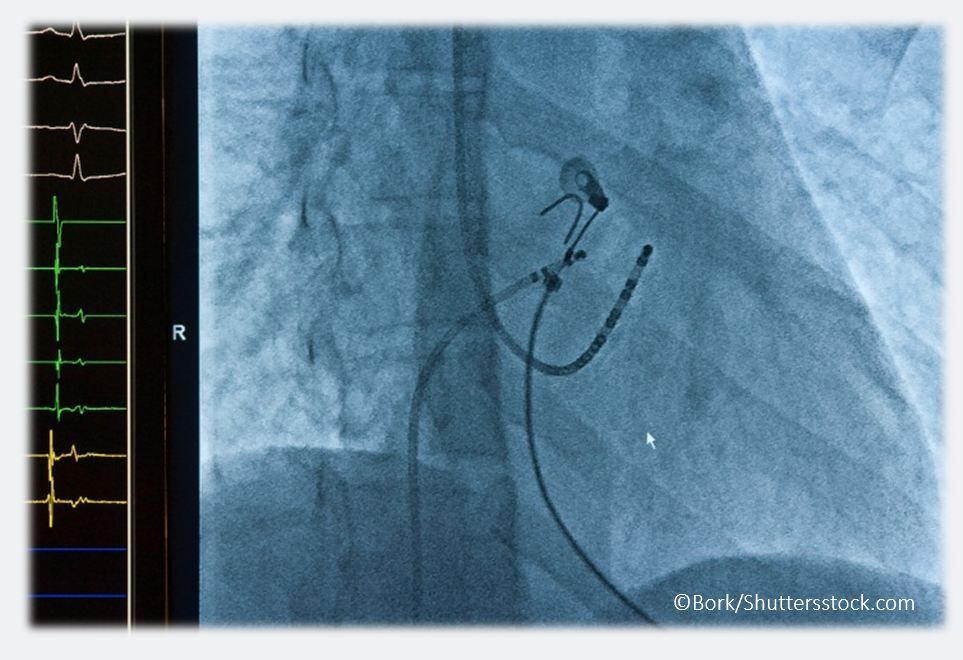

Ablation has become a leading option to arrest AF in many patients. Try 3 quick questions to test your ablation quotient.